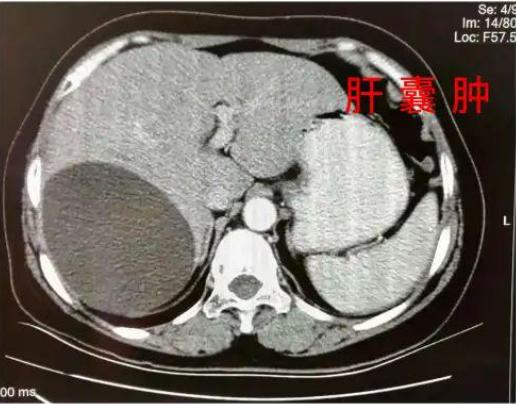

大学毕业后,通过打拼,条件改善了,但是由于身体基础差,又患上了肝囊肿,卵巢囊肿等疾病。工作时候,由于过于拼命,多次晕倒被120抢救!